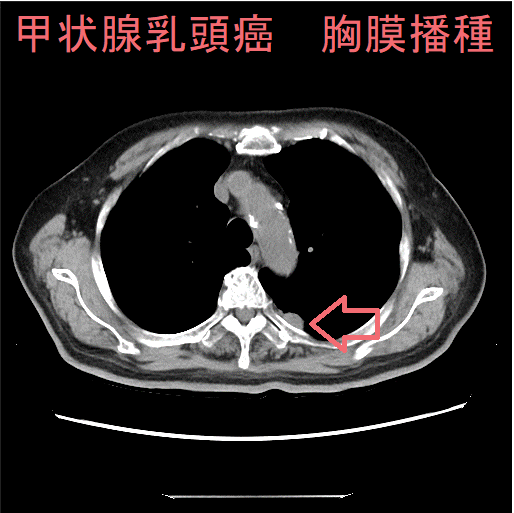

甲状腺乳頭癌の多発性肺転移に伴い、胸膜転移(胸膜播種、癌性胸膜炎、癌性胸水)が起こります。ただし、肺転移を認めないのに対側(甲状腺癌が無い側)に起こる場合もあります。

胸部CTでは、胸膜腫瘍[胸膜転移(胸膜播種、癌性胸膜炎、癌性胸水)]と同側の胸水貯留(癌性胸水)を認めます。重度の甲状腺機能低下症があれば、粘液水腫による胸水も考えねばなりませんが、その場合、胸膜腫瘍(胸膜播種)は無く、甲状腺ホルモンが正常化すれば胸水も消失します。

胸膜転移(胸膜播種、癌性胸膜炎、癌性胸水)では、胸部打診で濁音を示し、呼吸音が弱くなり、聴診で胸膜摩擦音が聞かれます。

胸膜転移(胸膜播種、癌性胸膜炎、癌性胸水)の診断は、

- 胸水細胞診で甲状腺乳頭癌細胞塊を確認。免疫染色では、サイログロブリン、TTF-1(甲状腺転写因子)が陽性に染まります。TTF-1(甲状腺転写因子)は、大部分の小細胞肺癌、原発性・転移性肺腺癌でも発現するため、肺癌との鑑別には不向きと言えます。

- 胸水中のサイログロブリン値が上昇するのも有用(日本臨床, 47:1147-1150, 1989.)